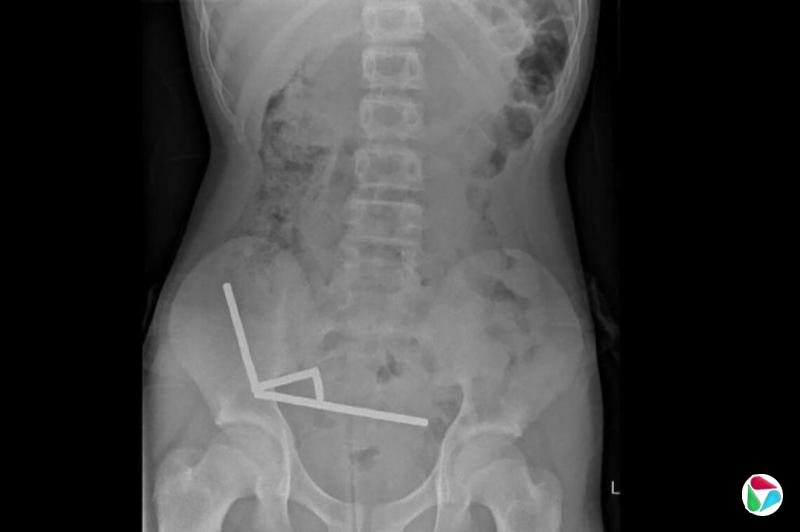

X光片显示在男童肠道里的钕铁硼磁铁黏连成四条直线。医生说:“这些磁铁似乎位于肠道里的不同区域,因为磁力作用而粘连在一起。”

医生说,钕铁硼磁铁的压力导致男童的小肠和盲肠的四个区域坏死。外科医生切除了坏死组织并取出磁铁。